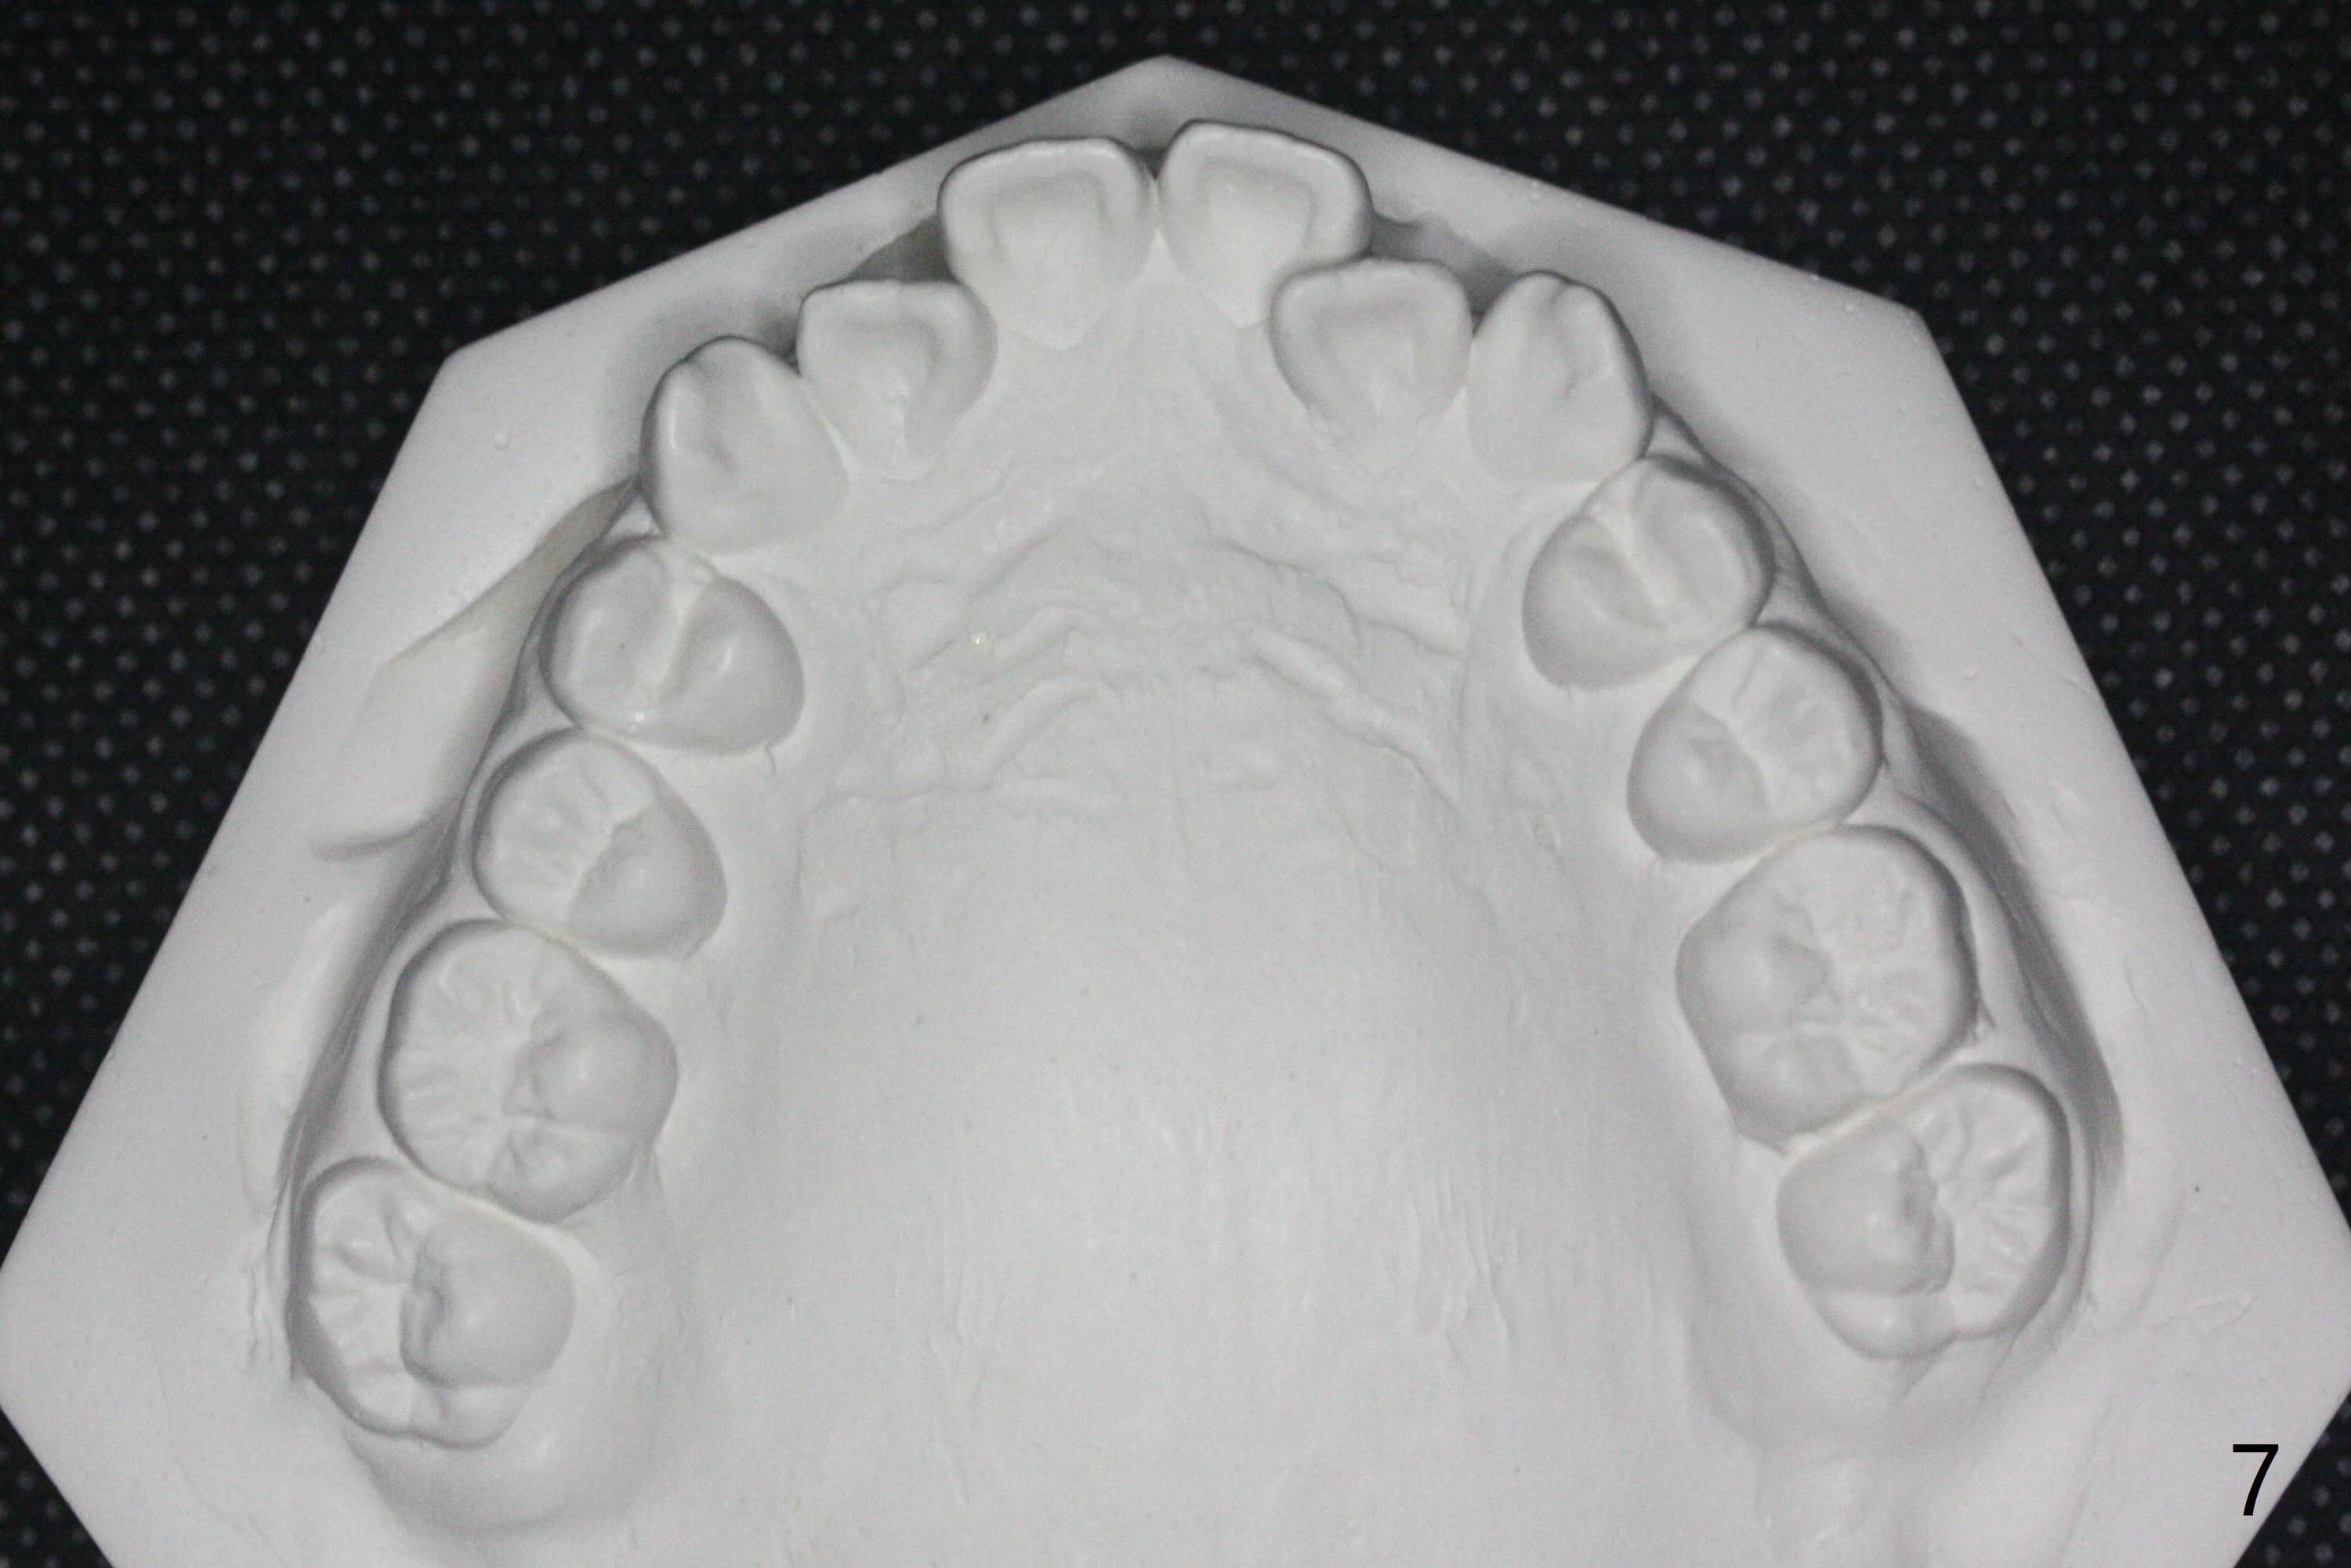

15岁男完成矫正1年9月,右侧后牙咬合理想(图二),上中切牙长轴改善,侧切牙torque不够完善(图四),左侧后牙咬合二类𬌗(图六,需要牵引),磨牙缝隙大(图八,十),造成食物堵塞,以后尽量避免使用磨牙bands,尤其是成人。